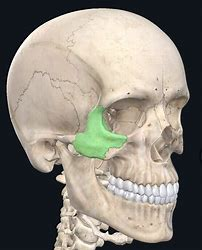

Greater wing of the sphenoid bone (“sphen”=wedge)

Greater wing of the sphenoid bone (“sphen”=wedge)